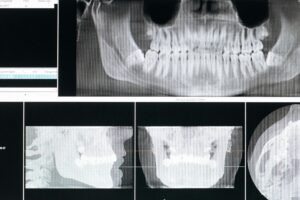

CBCT in Dentistry: Safety and Benefits

Learn about the safety and benefits of CBCT imaging in dentistry, including what it shows and important radiation considerations in Glendale, AZ.